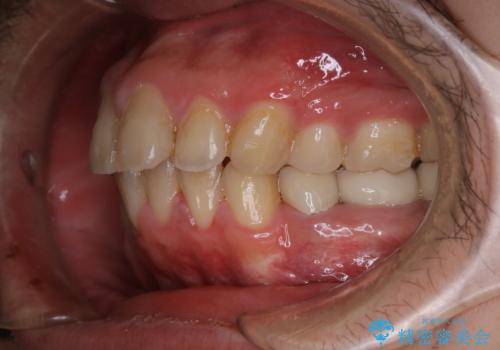

インビザライン矯正治療のスキャニング前のPMTC

- インビザラインでのスキャニング前にPMTCを希望されました。PMTC60分コースを行いました。

矯正治療前には、PMTCで歯石や汚れを取り除き、健康的な歯肉の状態にすることが大切です。PMTCでは、がたつきになどより、ご自身では取り切ることのできない細かい部分などに付着した汚れなども、専門的な機械や材料を使用してクリーニングを行います。